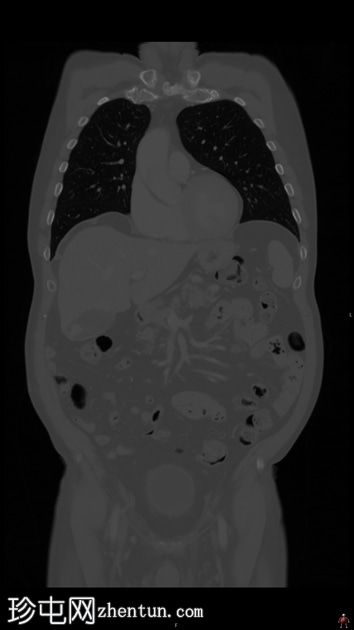

高危肾细胞癌分期CT检查。

轴位增强扫描(C+)门静脉期

行CT检查以进行分期。已知肾细胞癌。已行右侧根治性肾切除术和左侧肾上腺切除术。胆囊内可见强化物质,提示胆囊底部血管受累。骨窗下胆囊内未见钙化灶。影像表现提示胆囊转移。